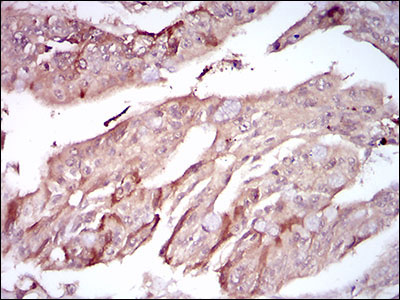

PON1 Antibody

| WB, IHC, FC, E |

| Dilution | WB~~1/500 - 1/2000 IHC~~1/200 - 1/1000 FC~~1/200 - 1/400 E~~1/10000 |